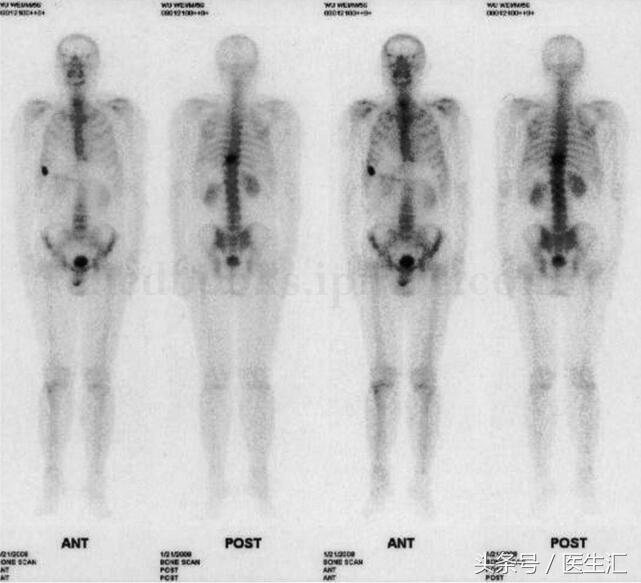

图21‐1 全身骨扫描示右第7 前肋及第9 胸椎放射性异常浓集

影像学检查:全身骨扫描示右侧第7 前肋及第9 胸椎放射性异常浓集,骨骼其余部位未见转移性病灶(图21‐1)。CT 示第9 胸椎体溶骨性破坏,局部可见软组织肿块。MRI 示第9胸椎体骨质破坏,软组织肿块形成并向右后方突出,相应水平椎管狭窄,胸髓受压变形,与肿物分界不清,增强扫描后见肿物强化明显且不均匀(图21‐2)。